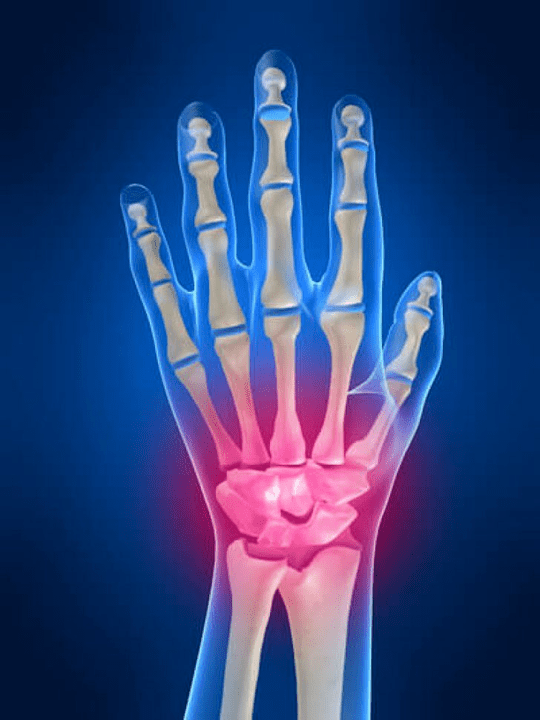

Anatomia delle articolazioni della mano

Tutte le articolazioni della mano sono consuete per essere divise nei seguenti gruppi:

- giunto al polso;

- articolazioni del polso;

- articolazioni del carpale;

- articolazioni interpendiali;

- Articolazioni parlemona-falange;

- Articolazioni interfalanx.

L'articolazione del polso

L'articolazione del polso è formata dalle ossa delle ossa prossimali (superiore) un certo numero di polsi (ossa trihedrali, semi -moon, scafoidi) e aree distali di radiazioni e ossa del gomito. L'osso del gomito non è direttamente collegato alle ossa del polso, ma con l'aiuto di distale (Inferiore) il disco articolare. Questa struttura separa la cavità dell'articolazione del polso dalla cavità distale (Inferiore) L'articolazione delle piastrelle.